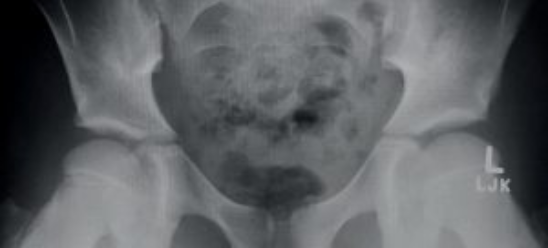

以下の写真は、現在14歳になる若いダンサーのものです。10歳から股関節の痛みを感じ始めました。X線写真を撮り検査しましたが、何も悪くないと言われたそうです。(彼女のバレエ教師は、股関節に痛みがあるのは付き物!と言ったそうです)彼女は継続して股関節の痛みを抱えたままでしたので、私に出会うまで13歳と14歳でも再びX線写真を撮影していました。

下の写真をよく見てみましょう。彼女がバレエ学校で行っていた行き過ぎたストレッチによって、股関節の受け皿が移動してしまっています。すでに石灰化してしまっていますので、一生このままの形状です。

この2つの写真は、この生徒が10歳の時

股関節の受け皿がまだ未成熟なのが見てわかりますね。股関節が形成されている部分には、骨盤の骨との間に隙間があります。これは骨折ではなく、骨盤が発達する時に起こる自然のプロセスです。彼女が行なっていたストレッチのエクササイズによって、2つの骨同士の配列がずれてしまった事が問題です。

同じ生徒の13歳の時の写真

13歳になっても股関節の痛みを訴えていたので、再度X線写真を撮影する事になりました。下の写真では、股関節の受け皿のダメージが鮮明に見えますね。

黒い線は股関節の受け皿の表面で問題が起きている所を示し、大腿骨の成長板に過剰な動きがある証拠です。過剰な負荷によって、大腿骨頭は本来あるべき丸みを失い、平らになってしまっています。

同じ生徒の14歳の時の写真

14歳でもまだ股関節の痛みがありましたので、再度撮影が行われました。またその頃に、継続する痛みの治療の為にパーフェクト・フォーム・フィジオセラピーへ行くことを彼女の友人に勧められています。

これらの写真では骨盤の骨が融合し始めていますが(本来そうなるべきである)、大腿骨の先端(腿の骨)は平らになり、股関節の受け皿がとても浅くなっています。またここでは、一つ前のX線写真にはない、股関節の上の所に股関節の前のインピンジメント(つまり)の原因となる、股関節の上の所の”過剰な骨が形成”が見られます。

骨は負荷に対応して発達していきますので、おそらく、右脚を繰り返して上げた事により圧縮負荷への反応として、過剰な骨が育成してきたと思われます。

この少女の将来はどうなってしまうのか?

この少女は股関節前のインピンジメント(つまり)と股関節の受け皿の骨の変形により、痛みと共に生活する事になるでしょう。そして、早い時期で人工股関節の手術をする必要があります。細心の注意を払ったリハビリによって、痛みのレベルを下げなければなりません。そして再び痛みなく踊る事が出来るようになるには、彼女自身がコツコツと努力して、真剣にリハビリに取り組まなければなりません。